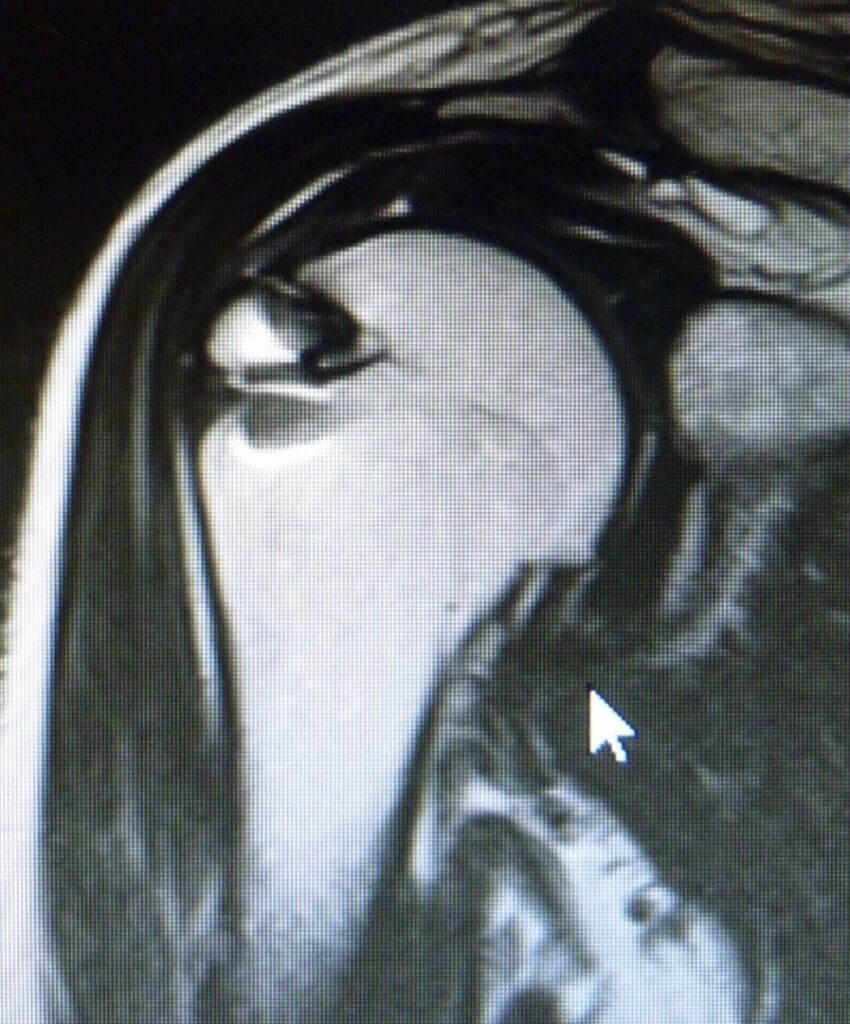

術後に再建腱板の評価をMRIで行います

菅谷分類

| Type1 | 腱板に厚み,一様に低信号 |

|---|---|

| Type2 | 腱板に厚み,一部に高信号混在 |

| Type3 | 連続性は保たれているが厚みがない |

| Type4 | 一部のスライスで連続性がない |

| Type5 | 連続性の途絶部分が大きい |

Type1(最もいい)~5(最も悪い)

4、5(再断裂)であっても求心位がとれていれば問題ありません。